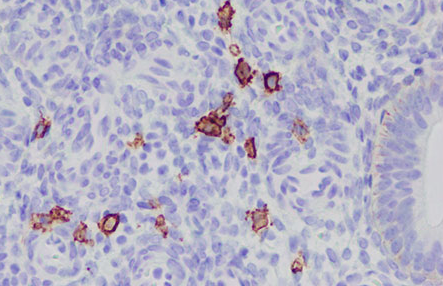

慢性子宮内膜炎の子宮内膜においてCD138という細胞マーカーが陽性の細胞(形質細胞)が認められます。子宮内膜組織を採取し、特殊な病理検査を行うことにより、慢性子宮内膜炎の診断を行います。

CD138 免疫組織染

この検査である程度以上のCD138陽性細胞が見られた場合を子宮内膜炎と診断することが現時点での主流ですが、必ずしも正確な検査ではありません。